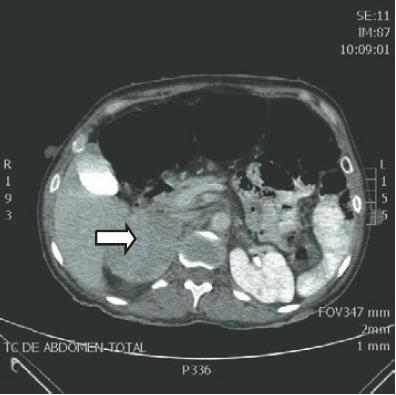

Para mais, os exames de imagem de escolha para diagnóstico do feocromocitoma são a tomografia computadorizada ou a ressonância magnética (RM). À RM, o feocromocitoma apresenta-se com hipersinal em T2. E ainda, a cintilografia é um exame muito eficaz na localização do feocromocitoma, bem como do paraganglioma, doenças metastáticas e múltiplos tumores cromafins.